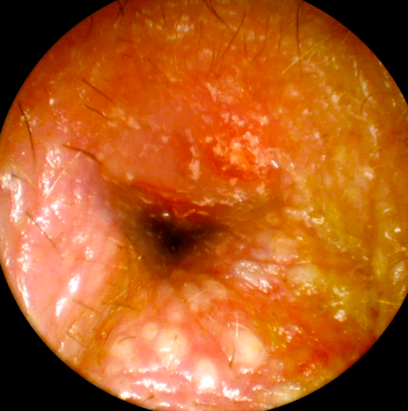

14

Q

A

Colesteatoma oido

( Epitelio queritinizante en oido medio con sustancias que producen osteólisis en oído medio )